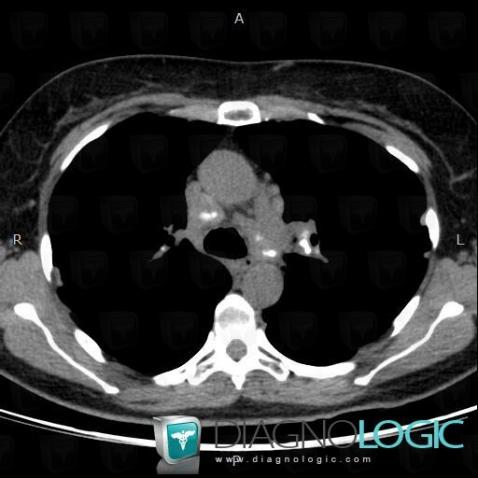

Voici les informations spécifiques à l'image clé ci dessus:

- Diagnostic Sarcoïdose, Localisation(s) Médiastin, comportant les gammes Adénomégalie hilaire

Voici les informations spécifiques à l'image clé ci dessus:

- Diagnostic Sarcoïdose, Localisation(s) Médiastin, comportant les gammes Adénomégalie hilaire